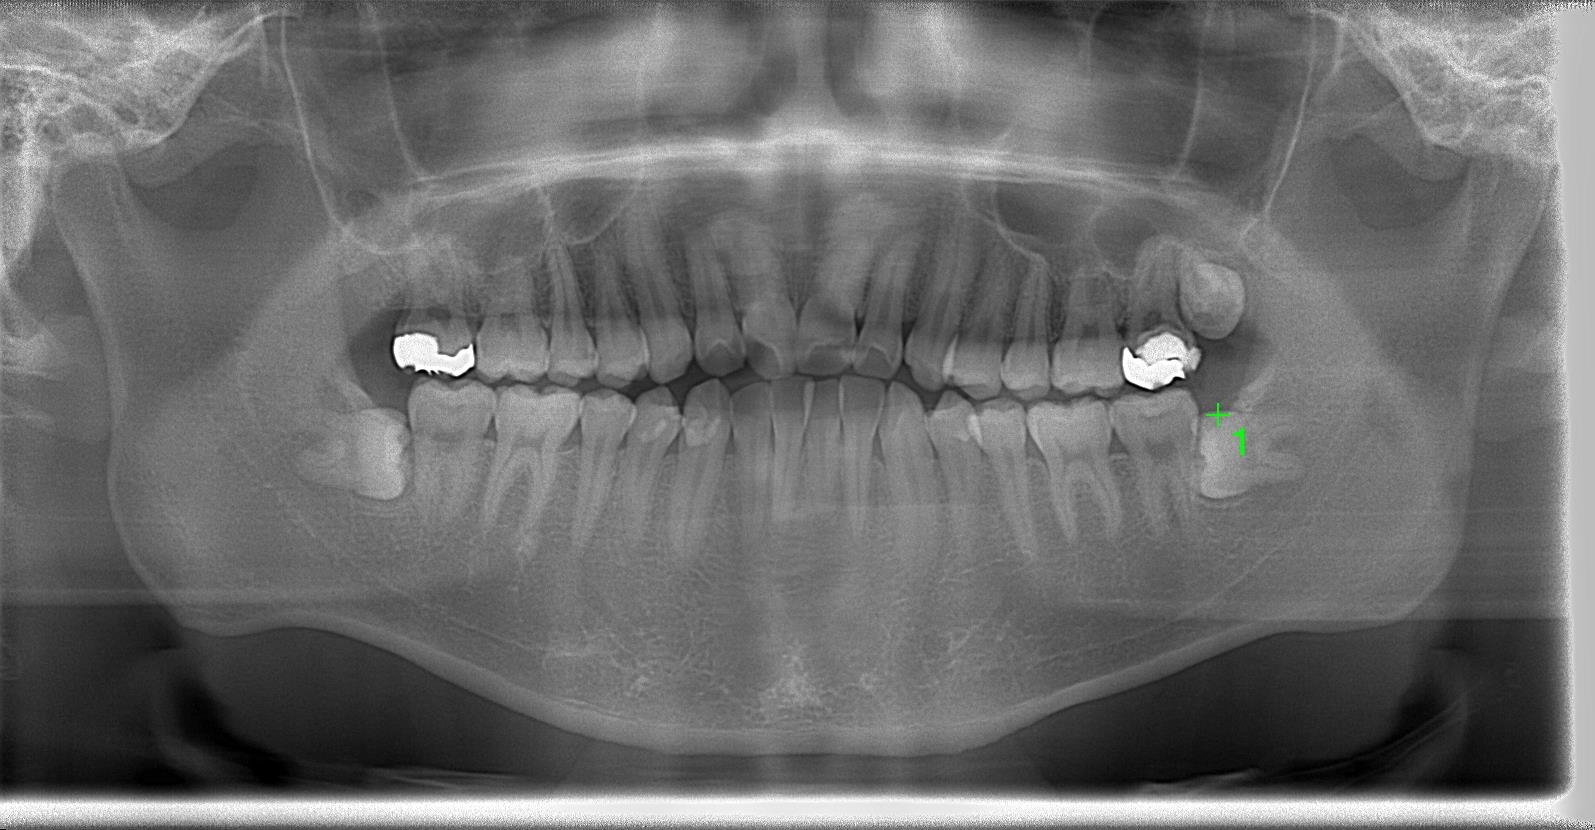

レントゲン写真の状態を御覧ください。

術前

部位:左上8番骨性完全埋伏歯

部位:左下8番骨性完全埋伏歯